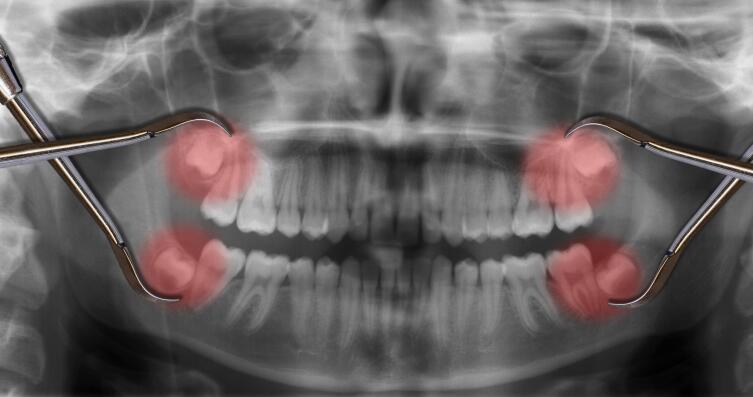

- По сравнению с другими зубами, зуб мудрости имеет большее количество корней — их количество может доходить до 5. Эта особенность нередко становится причиной проблем при его удалении.

- Значительная изогнутость корней, затрудняющая прочистку и пломбирование каналов.